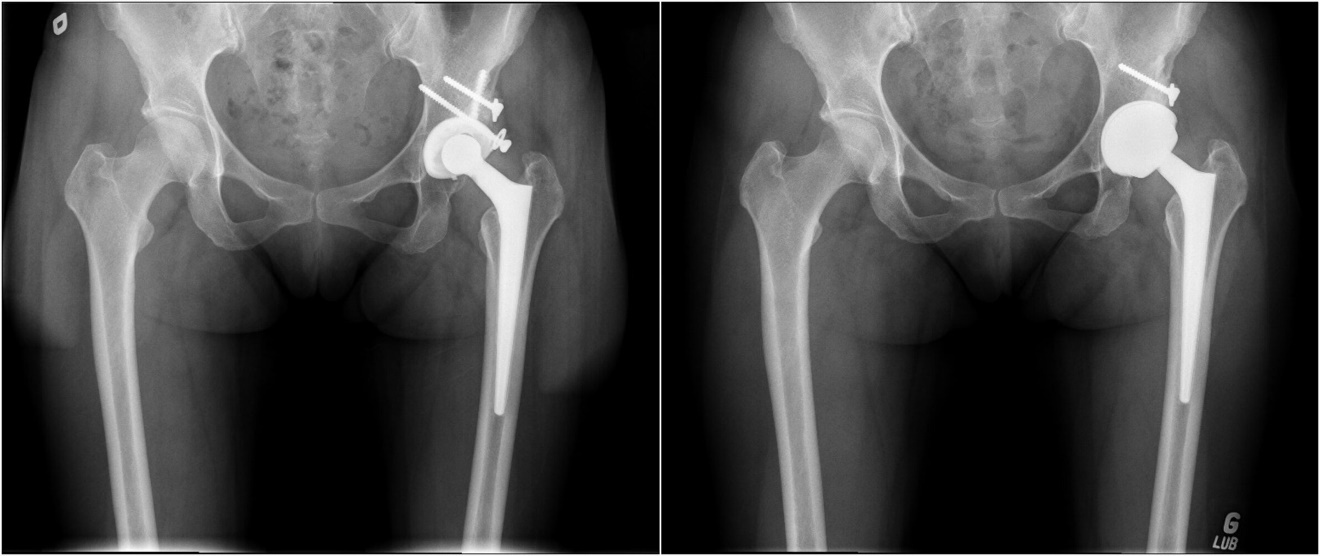

For this consecutive single-centre case series, the local arthroplasty database was used to retrospectively identify revision THA using press-fit only LDH monobloc acetabular components between 2007 and 2019. Inclusion criteria were a minimum follow-up of 2 years after revision THA and the availability of preoperative, postoperative, and last follow-up hip radiographs (Figure 1). Patients’ characteristics are summarized in Table 1.

The procedures were performed by five experienced arthroplasty surgeons in our academic institutions. All revision THAs were performed using a posterior approach. The revision was limited to the acetabular component in 26 hips (55%). To retrieve the primary femoral stem, a femoral osteotomy was required in 3 cases (6%). To limit acetabular host bone deficits, the Explant (Zimmer Biomet, Warsaw, Indiana) was used to retrieve the acetabular cup. Allografts were used in 16 cases (34%) to augment acetabular deficits. Press-fit fixation of the acetabular component was obtained by 1 to 2 mm under reaming versus the implant’s outside diameter. Press-fit between the anterior and posterior acetabular rims was achieved in cases where a superior rim deficit was present. One such technique to achieve this was to medialize the implant to increase anterior and posterior rim contact. If superior contact was the preferred option where smaller defects were present; the center of rotation for the hip was elevated by 10 mm. Examples of these principles are demonstrated in Figure 2 and Figure 3.